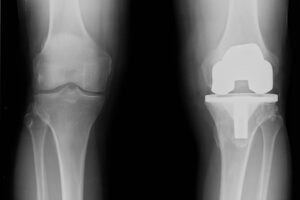

La protesi di ginocchio è un dispositivo artificiale che sostituisce parzialmente o completamente l’articolazione danneggiata. L’intervento viene generalmente indicato nei casi in cui il dolore e la rigidità articolare non rispondono più alle terapie conservative o ai trattamenti di Medicina Rigenerativa.

La condizione che più frequentemente porta alla sostituzione protesica è l’artrosi di ginocchio in fase avanzata, ma l’intervento viene eseguito anche in casi di esiti particolarmente gravi di traumi articolari, deformità o necrosi ossea.

L’obiettivo dell’intervento è eliminare il dolore, migliorare l’allineamento dell’articolazione e ripristinare la funzionalità del ginocchio. Tuttavia, senza un adeguato percorso di fisioterapia, il ritorno alla vita quotidiana potrebbe essere più difficile.